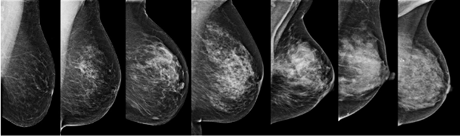

On mammograms, dense breast tissue looks white. Breast masses or tumors also look white, so the dense tissue can hide some tumors. In contrast, fatty tissue looks almost black. On a black background it’s easier to see a tumor that looks white. So, mammograms can be less accurate in women with dense breasts.